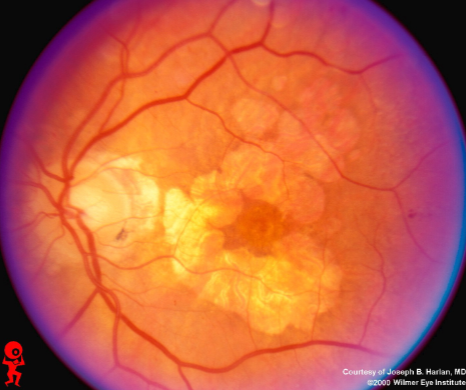

geographic or central areolar RPE atrophy

a form of dry AMD consisting of large areas of GA of the RPE

histologic: the area of GA is associated w/ focal loss of the retinal receptor cells, RPE, & choriocapillaris

5-10% of pts w/ AMD lose central vision as a result of this form of AMD

one or more sharply circumscribed geographic areas of atrophy of the RPE & retinal in the posterior pole

central vision is slow & progressive as the atrophic concentric area enlarges

bilateral, symmetric

20% of these pts will develop CNVM in the 2nd eye

FA shows varying degrees of loss of the choriocapillaris w/in the area of GA

GA

GA

GA

GA

GA